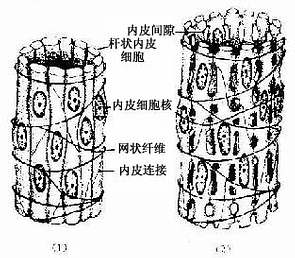

脾血窦(splenic sinus):是一种静脉性血窦,宽约12~40μm,形态不规则,相互连接成网。窦壁由一层长杆状的内皮细胞平行排列而构成。内皮细胞之间常见许多0.2~0.5μm宽的间隙,脾索内的血细胞可经此穿越进入血窦(图9-21,9-22)。内皮外有不完整的基膜及环行网状纤维围绕,故血窦壁如同一种多孔隙的栏栅状结构。在血窦的横切面上,可见杆状内皮细胞沿血窦壁呈点状排列,较粗大的内皮细胞断面中可见有细胞核,并突入管腔(图9-19)。血窦外侧有较多的巨噬细胞,其突起可通过内皮间隙伸向窦腔。

图9-21 脾血窦结构示意图

(1)收缩状态 (2)扩张状态